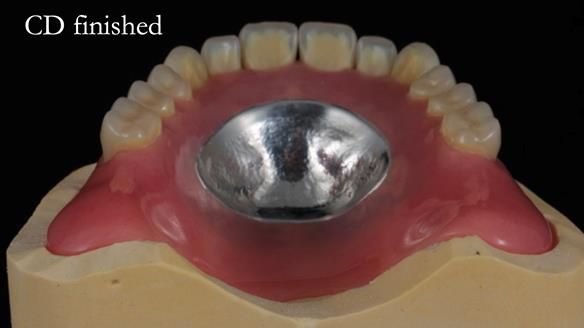

The detailed clinical situation and treatment process are outlined below, with clinical work provided by me and technical work by Rowan Garstang. The treatment spanned 12 months, involving removing 5 upper anterior teeth, adding to an existing upper RPD, followed by creating and fitting metal based complete dentures.